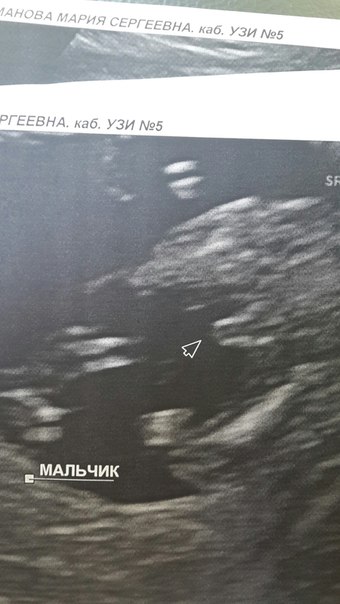

Мария

Вот наше "хозяйство" в 15н5дн выглядит внушительно.:)

Да, точно!!! И сроки такие же)) Вот, значит, как этот огурчик выглядит)))